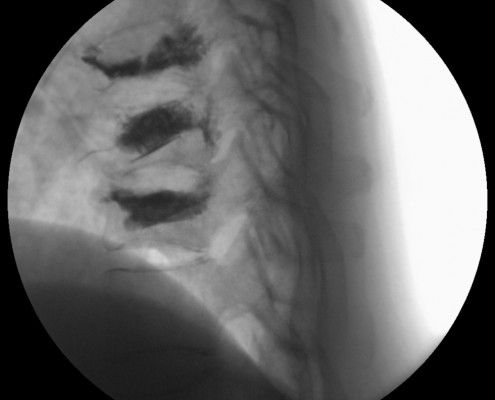

Puedes ver imágenes de una fractura y de la técnica quirúrgica de un caso real del 2015 tras este texto.